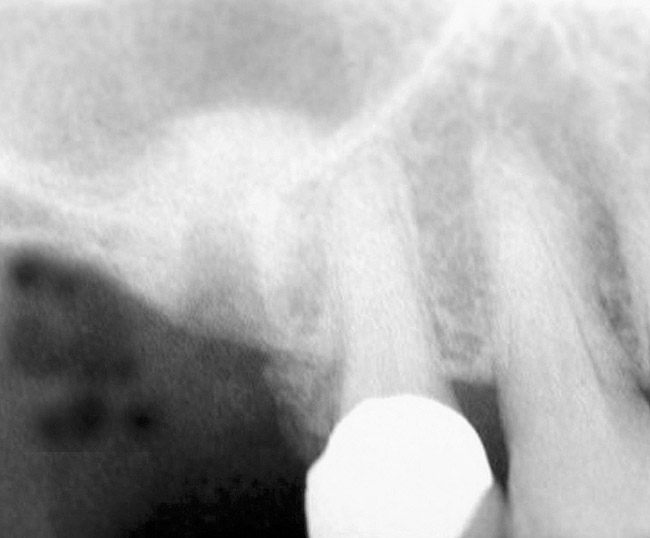

The 2-mm twist drill is used to create an osteotomy 1 mm short of the subantral floor. If any resistance is detected prior to reaching the 3-mm depth, drill penetration must be stopped, because the subantral cortical bone has possibly been reached. Any uncontrolled "push" would penetrate the bone and likely perforate the sinus membrane. A guide pin is then inserted and a radiograph taken to determine if drill penetration has terminated within 1 mm of the subantral floor (Figure 2). If the radiograph indicates that more than 1 mm of bone is present subantrally, the twist drill is used again to penetrate within 1 mm of the sinus floor. Alternately, an osteotomy tip for a piezosurgery unit can be used for this purpose. The final depth of penetration should be verified with another periapical film.

Figure 2  After drilling to a depth of 3 mm with a 2.1-mm twist drill, the guide pin was placed and a radiograph was taken to ascertain if the drill stopped within 1 mm of the subantral floor.

Figure 2